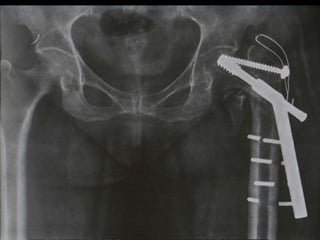

Failed

Subtrochanteric

fracture fixation

with broken DCS

and plate

After 51 days